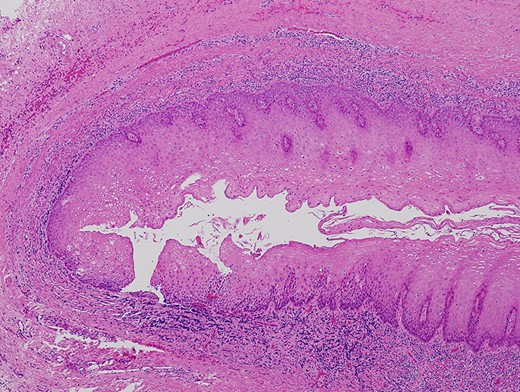

A 66-year-old man was referred to our institution in January 2018 for the diagnosis and treatment of a right buccal lesion. The lesion was first noticed approximately 1 month previously during an examination by his family dentist. The patient’s medical and family histories were unremarkable. He had no history of trauma to the face. Physical examination revealed bruising on the skin of his right cheek (Fig. 1). In the oral cavity, a mucosal outpouching (5-mm diameter, 10-mm depth) was observed in his right cheek. Food debris was seen in the outpouching (Fig. 2). The adjacent overlying oral mucosa was normal in appearance. The clinical diagnosis was a diverticulum-like lesion of the buccal mucosa. Excision of the outpouching was performed through an intraoral incision to stop food impaction (Fig. 3). It was easily separated from the surrounding soft tissues and completely excised (Fig. 4). The bottom of the outpouching was over the buccinator muscle on the lateral side. The buccinator muscle layer and oral mucosal layer were sutured separately. Histopathological examination revealed that the excised lesion was a true diverticular structure composed of a keratinising, squamous epithelial lining with a surrounding fibrous connective tissue wall, with inflammatory cell infiltration and haemorrhage (Fig. 5). In contrast to the normal buccal mucous epithelium, the diverticular epithelium had a thick stratum spinosum appearance with formation of anastomosed rete ridges (Fig. 6). The surface of the parakeratinised epithelium was corrugated. The histopathological diagnosis was a diverticulum of buccal region. The postoperative course was uneventful.

Diverticular epithelium showing a thick stratum spinosum appearance with formation of anastomosed short and broad rete ridges and a corrugated epithelial surface (haematoxylin–eosin stain, ×40).

Oral diverticula are exclusively located on the buccal mucosa of older adults. Except for one large diverticulum reported by Bailey [3], oral diverticula are relatively small (≤15 mm in both diameter and depth). Clinical symptoms of an oral diverticulum include swelling [3], halitosis [5, 7], bleeding [3], and food impaction [7]. Three reported cases [4–6] were followed up with conservative treatment, and surgical excision was performed in another three cases [3, 7, 8]. The aim of the surgery was to stop food impaction into the diverticulum [7, 8]. In the present case, surgical resection was selected for the same reason. Histopathologically, the diverticular epithelium showed a corrugated surface layer and rete ridge formation. Such histologic architecture may suggest that the diverticular mucosa is able to expand. Inflammatory cell infiltration and haemorrhage were observed under the epithelium. These findings have not been documented in the English-language literature to date. However, bleeding has been reported as a clinical symptom of oral diverticulum [3]. In the present case, bruising on the skin of the right cheek and histopathological findings of chronic inflammation suggested the occurrence of subepithelial bleeding under the outpouching.